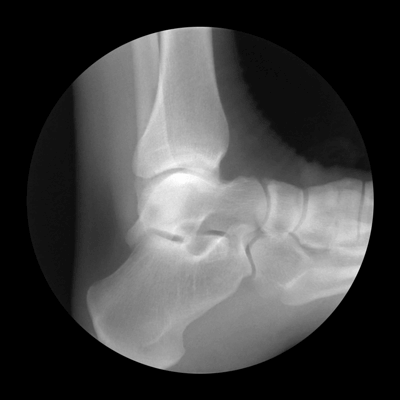

Οι παρακάτω φωτογραφίες, για την ακρίβεια πρόκειται για ακτινογραφίες του ορθοπεδικού Noah Weiss ο οποίος σε συνεργασία με τον φωτογράφο Cameron Drake, δημιούργησαν αυτές τις εκπληκτικές απεικονίσεις. Με τον τρόπο τους, ρίχνουν φως στο τι συμβαίνει στις αρθρώσεις.